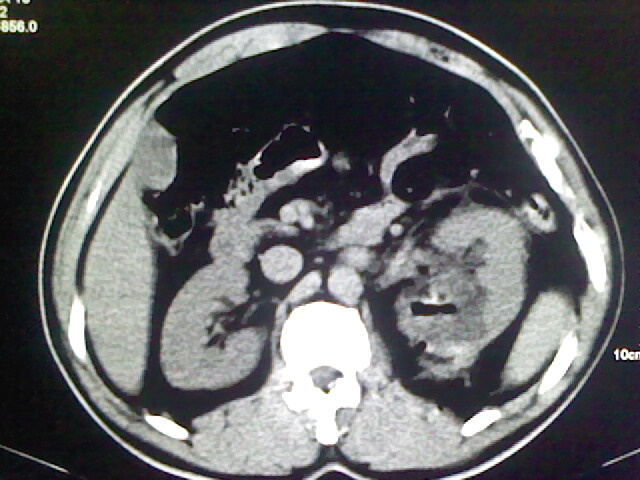

以下是引用zsl6918在2009-2-7 7:29:00的发言:[br]请提供介入的方式方法,肾及输尿管改变考虑与介入损伤有关,漏了,尿液外渗。

以下是引用余辉在2009-2-7 8:27:00的发言:[br]可能是硬化剂烧穿囊壁进入肾盂输尿管了,尿漏。不除外介入或碎石术后合并感染[br]患者术后怀疑结石,接着就碎石了?就怀疑没有确诊吗?碎石用的什么方法?气压弹道还是体外超声?如果这样的话责任人都难找

以下是引用随光逐影在2009-2-7 8:46:00的发言:[br]支持3楼意见。[br]另:不排除左肾及肾周感染可能。